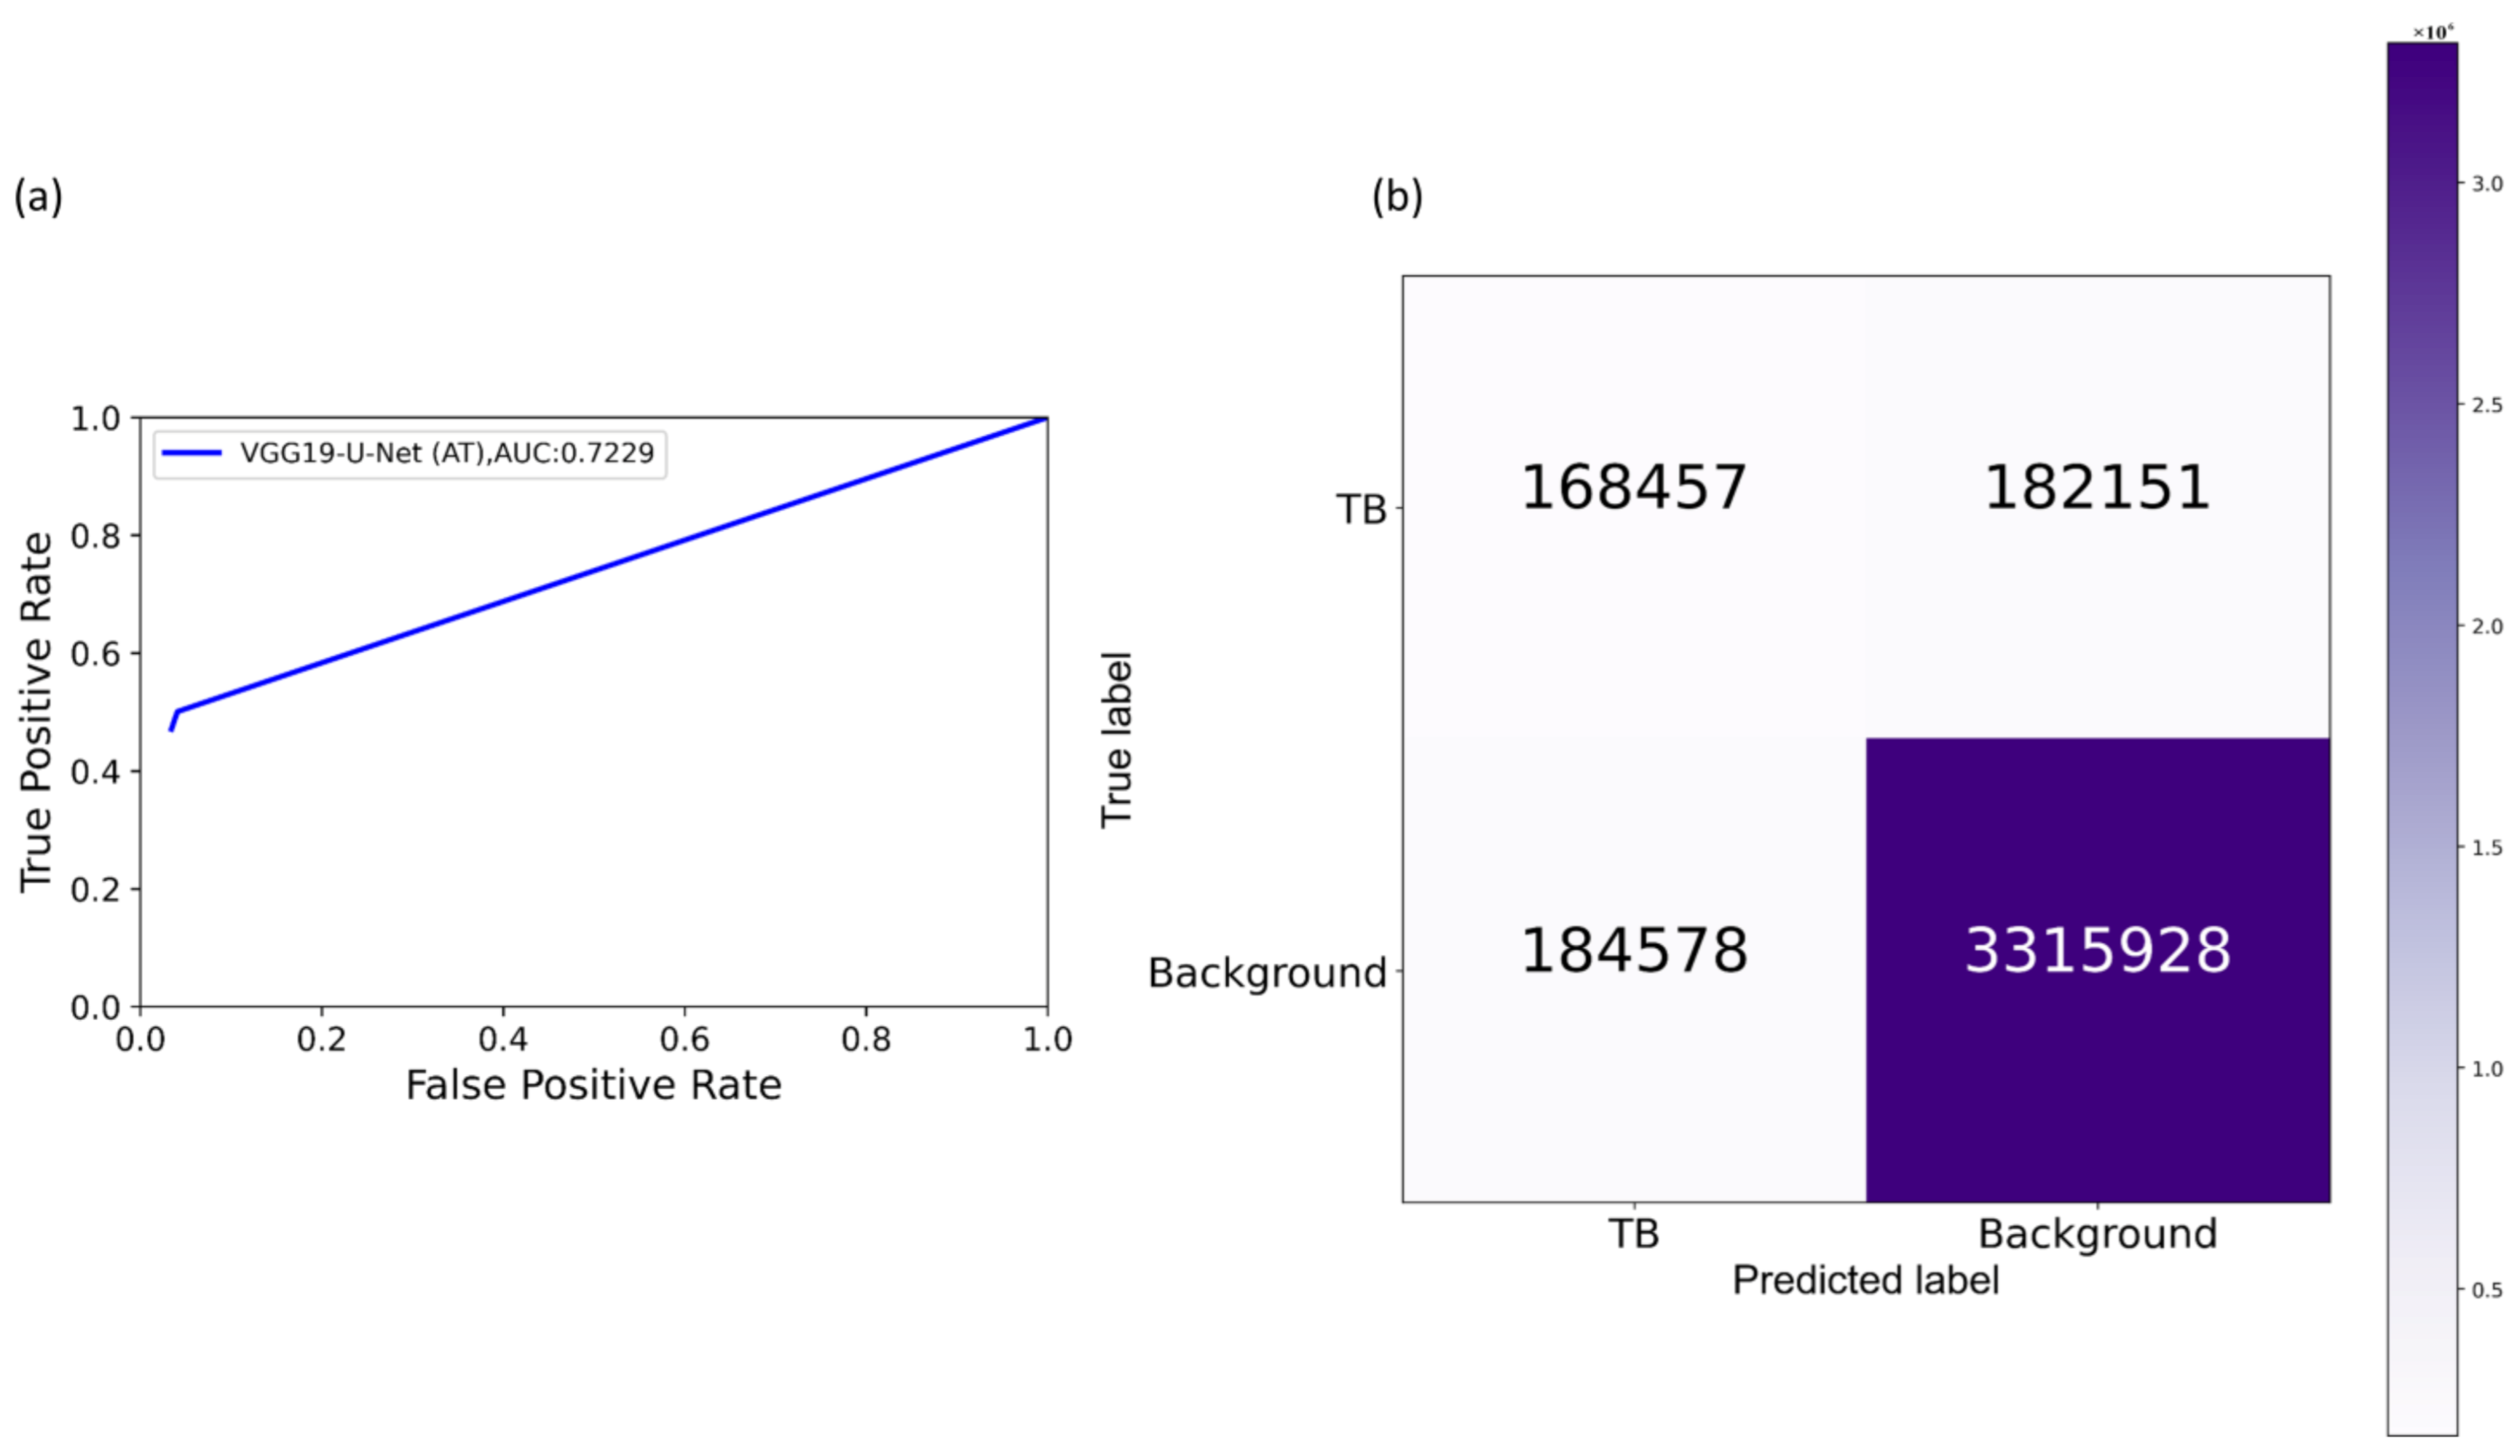

The following metrics are used to evaluate models’ performance during CXR modality-specific pretraining and fine-tuning stages: (a) accuracy; (b) AUC; (c) sensitivity; (d) precision; (e) specificity; (f) F-measure; (g) Matthews correlation coefficient (MCC); and (h) diagnostic odds ratio (DOR).